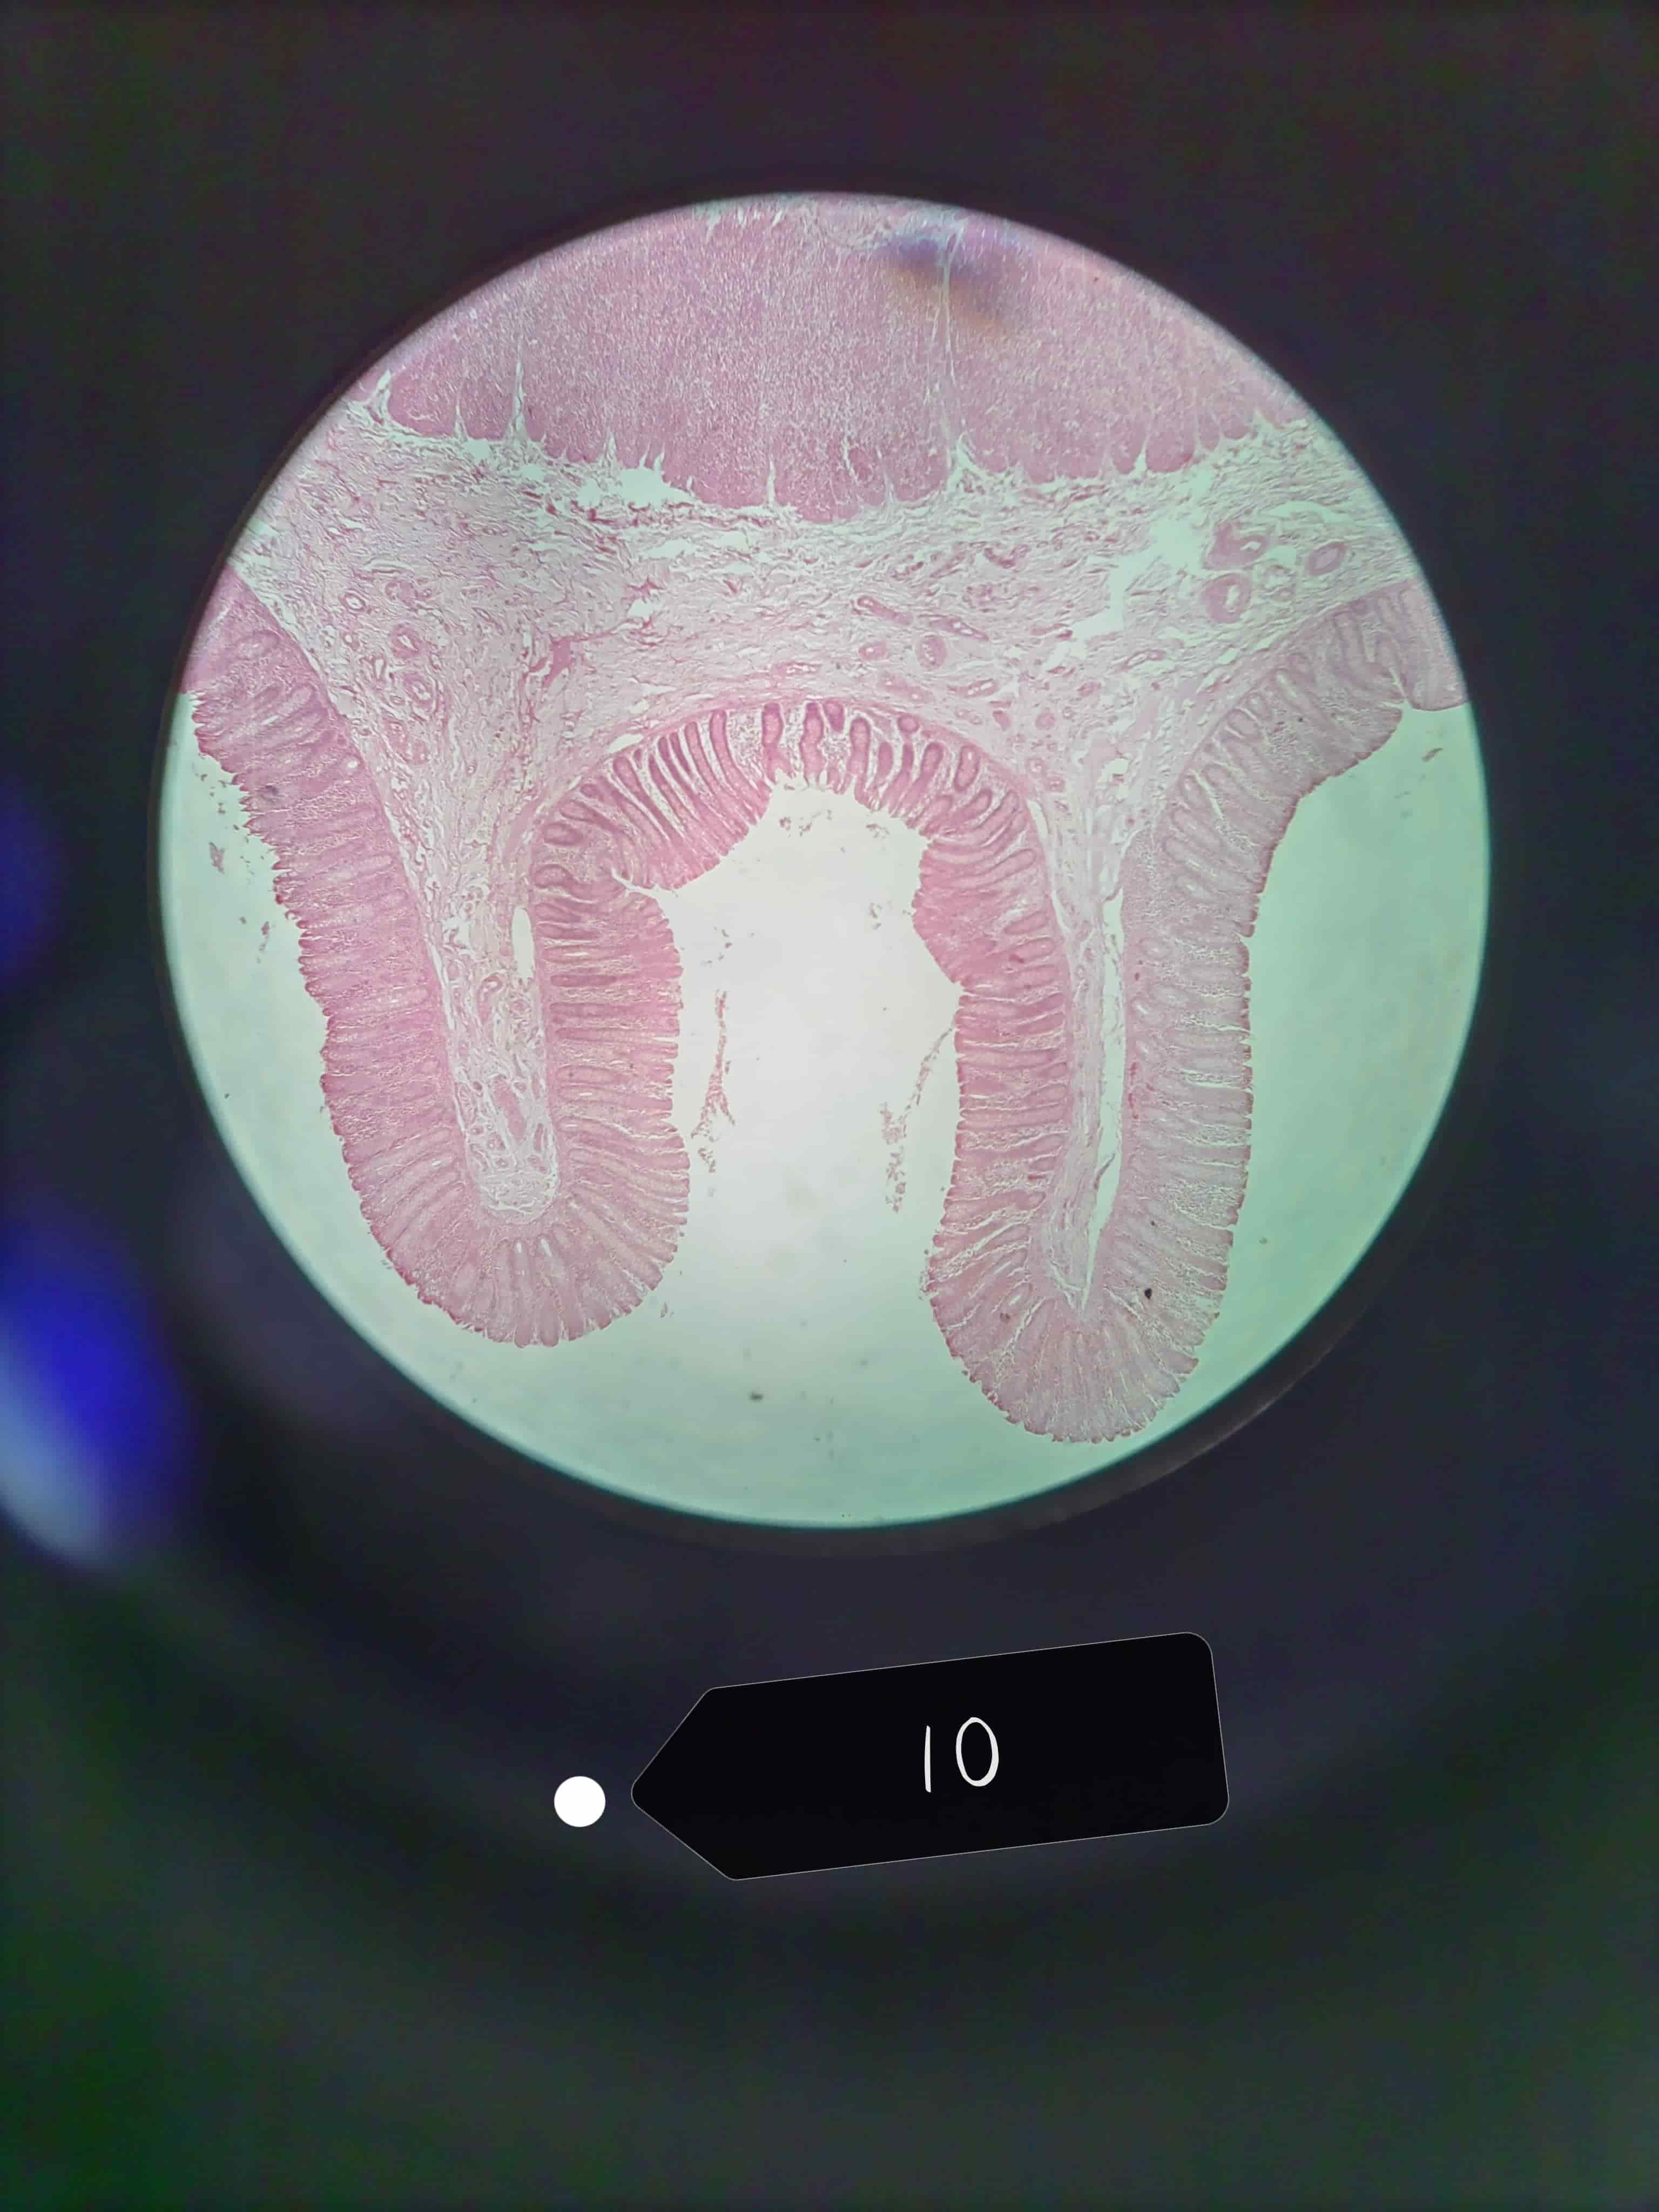

大肠

大肠腺

单层柱状上皮,杯状细胞较多